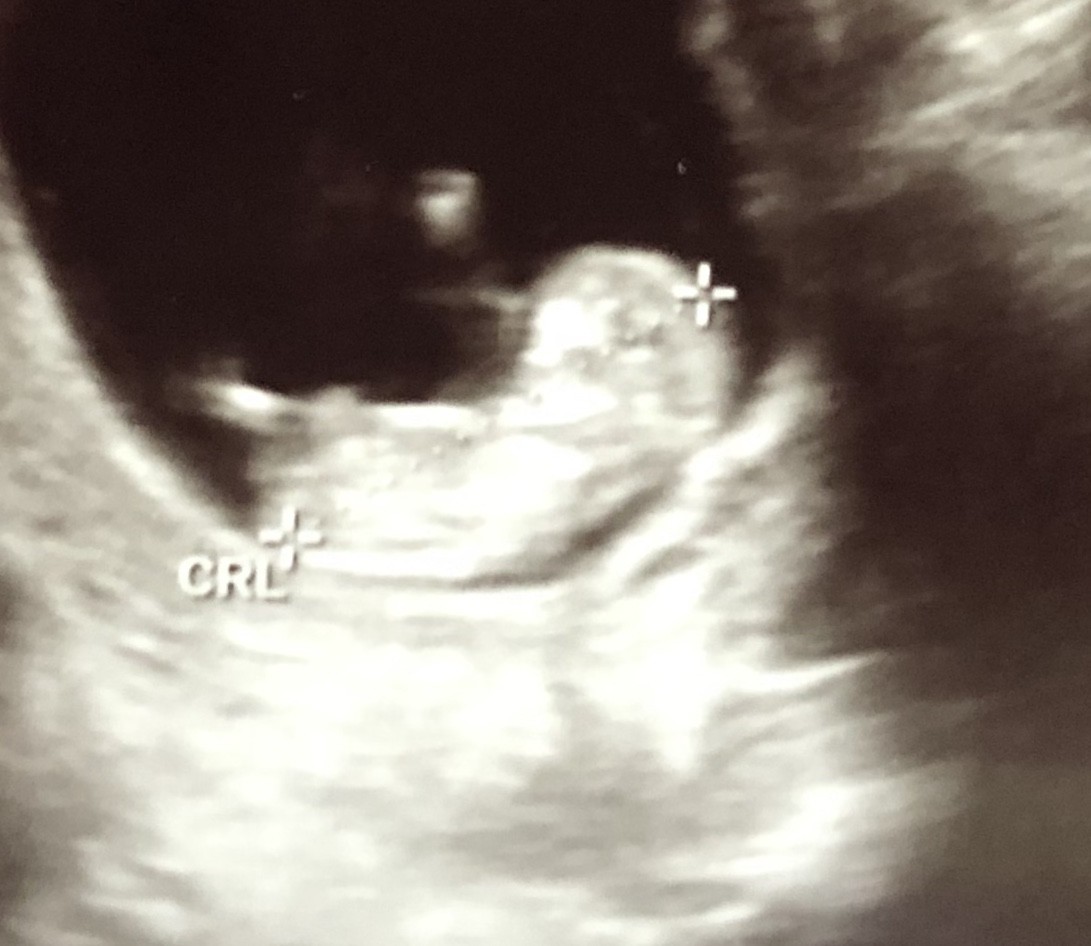

SadmiN ♥ Evli Mutlu Çocuklu ♥ Yönetici 20 Aralık 2019 #683 Malesef ilgili bölüm çok net değil yanlış bi tahminde de bulunmak istemiyorum cepten yakın çekip gönderebilir misiniz bi kaç tane çekin atın lütfen.

SadmiN ♥ Evli Mutlu Çocuklu ♥ Yönetici 20 Aralık 2019 #685 Yani çok net olmamakla birlikte erkek diyebileceğimi düşünüyorum.